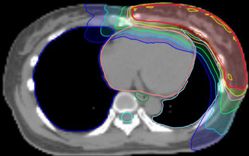

此外,由於螺旋刀無須使用等中心(ISO-Centric)的概念,又應用360度全方位調強的特性,因此劑量均勻分佈,比傳統IMRT更加優勝,對重要器官影響也更少。以下圖的乳房治療為例,螺旋刀能造出更好的弧形劑量分佈,以適合胸部 / 乳房的形狀,而肺部,心臟的劑量更少,減低後遺症。

除乳癌外,螺旋刀亦適合肺癌、肺膜腫瘤、前列腺癌、鼻咽癌、食道癌等。對於複雜外形腫瘤,多病灶轉移,腦及脊髓神經系統電療,或腫瘤復發需要作二次電療,尤為適合。